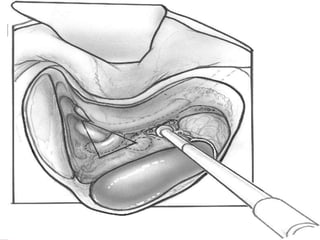

TRANSCANAL LABYRINTHECTOMY

Criteria

 Same as neurectomy

complications

 CSF leak

 Failure to find utricle

 Injury to facial nerve

 Incomplete labyrinthectomy

 Persistent vertigo(neuroepithelial remnant)

 Perform caloric test post op to find out

 Revision surgery